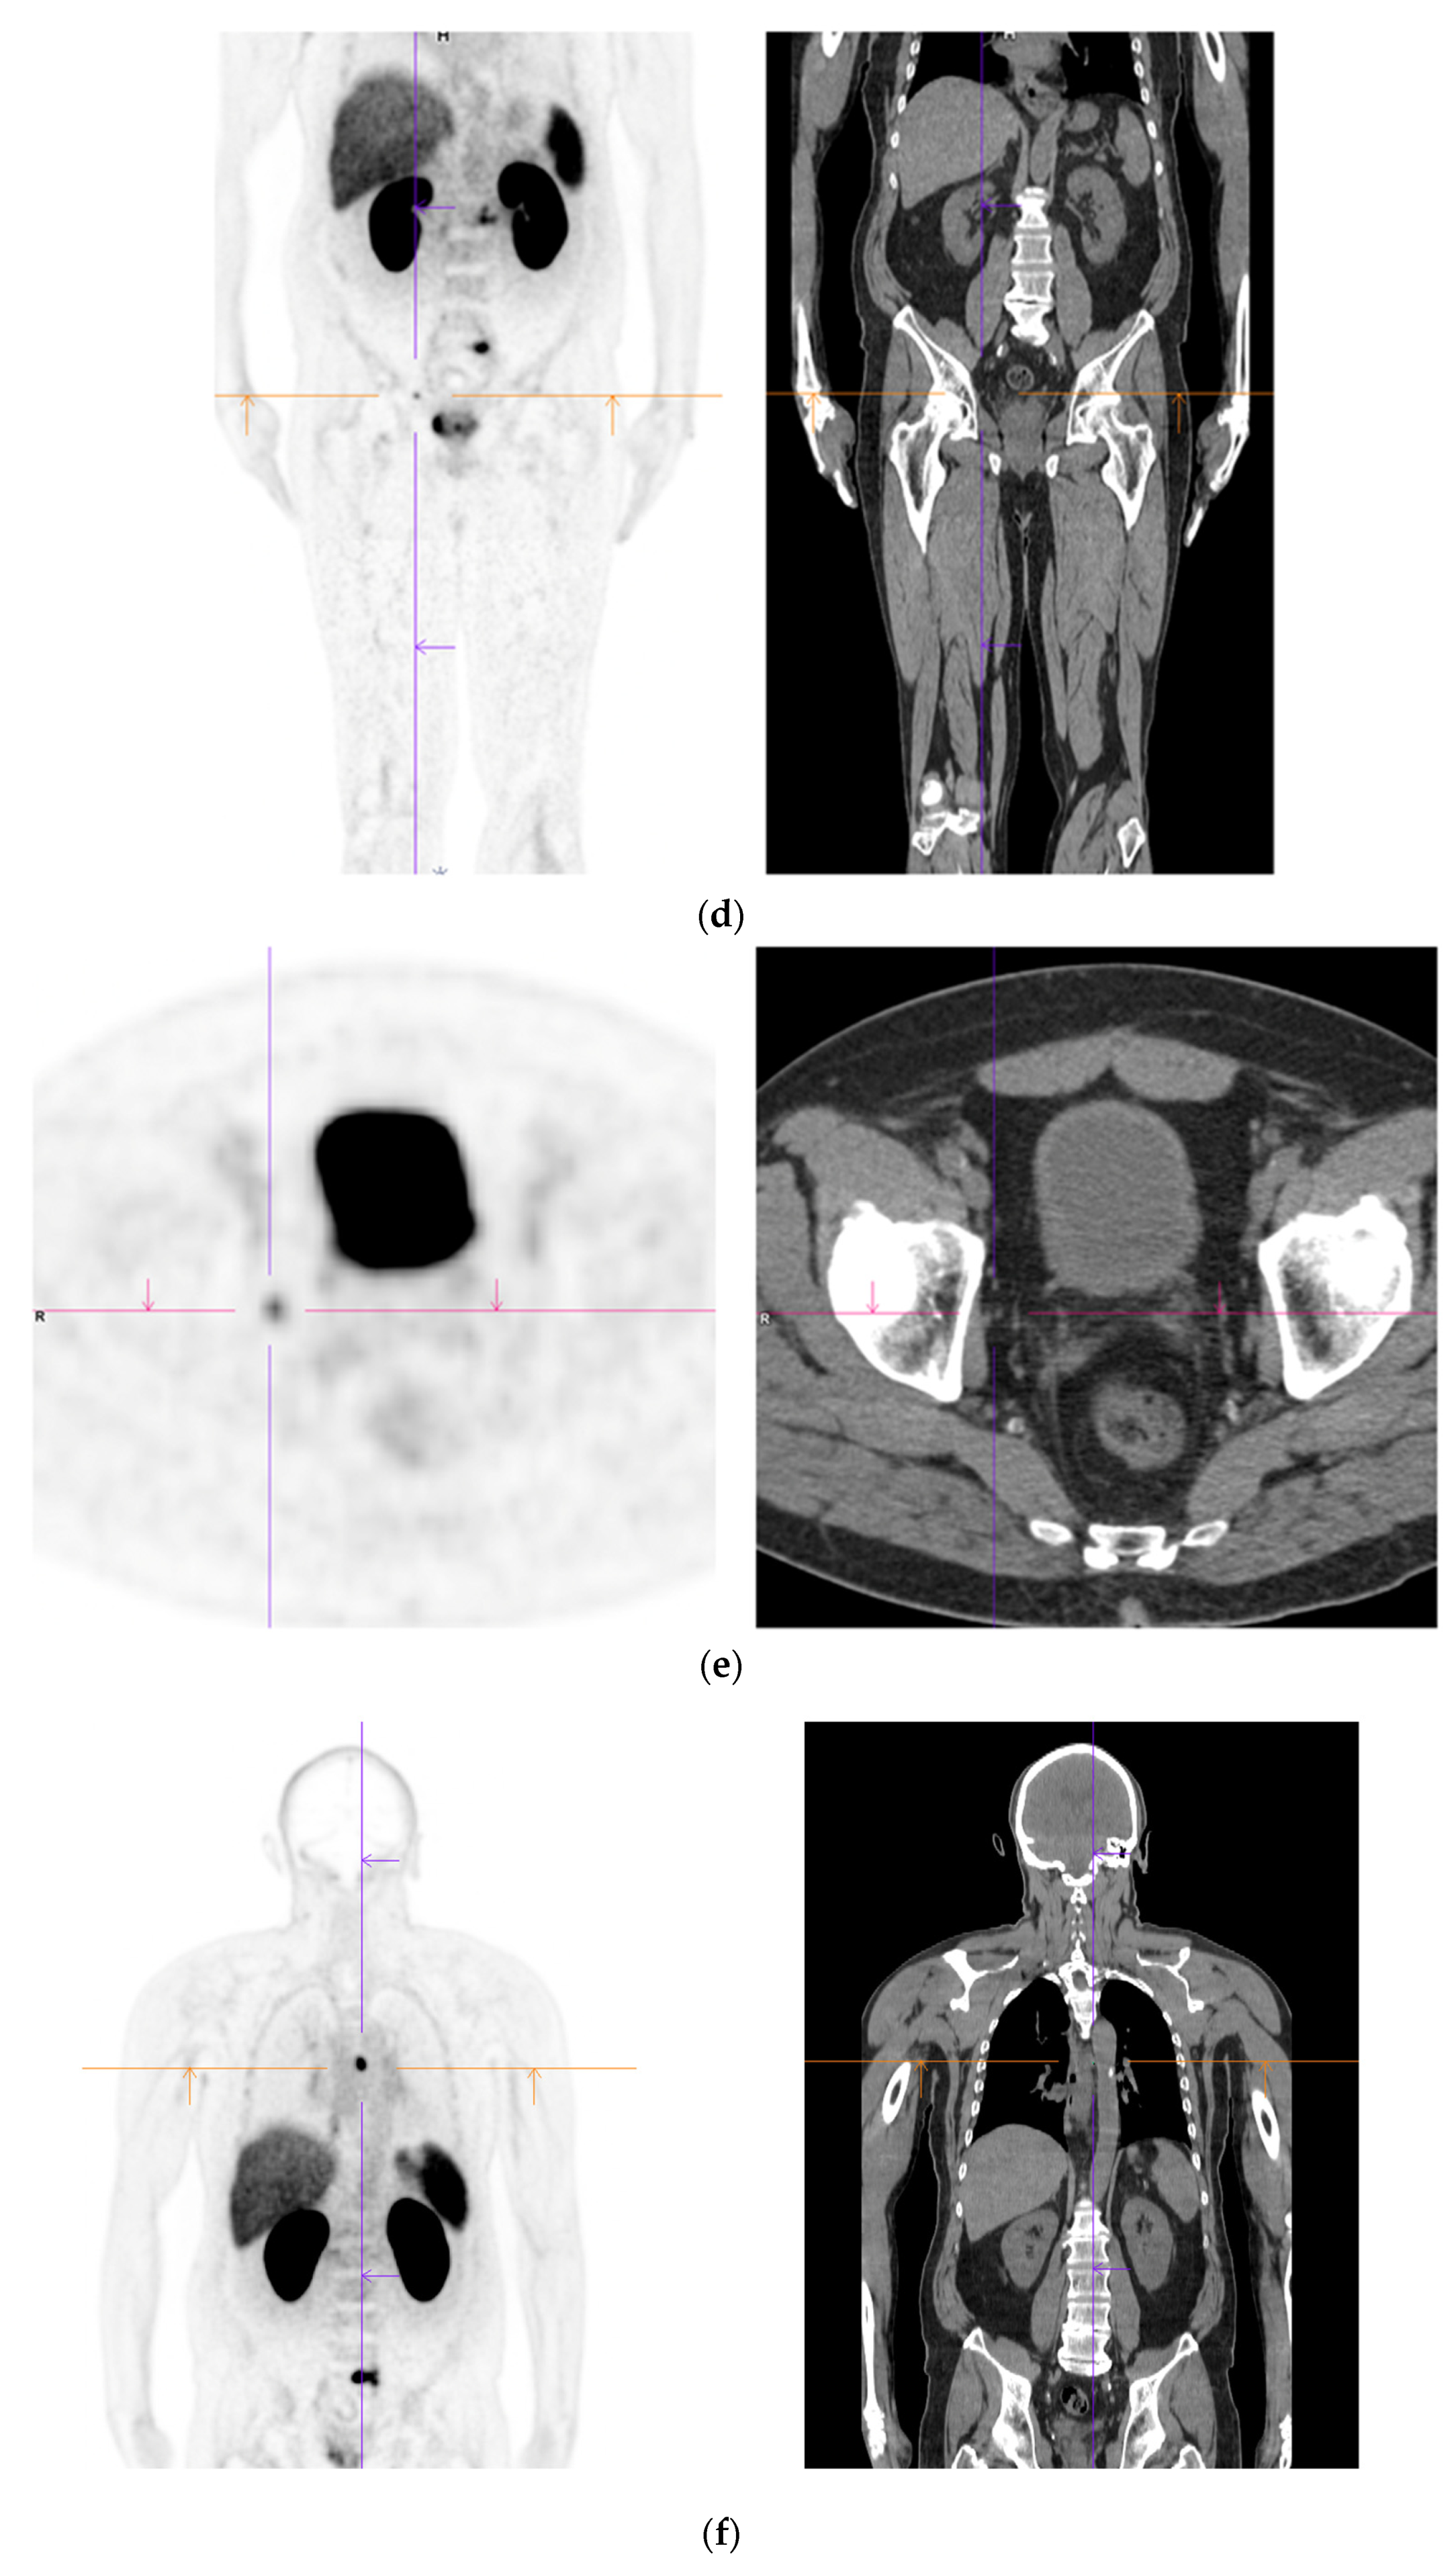

Figure 3.

Recurrent disease. 74 yr old M; radical prostatectomy 8 yrs prior; extensive para-aortic and upper pelvic lymph node involvement on CT; severe back pain; PSA 60. PSMA PET-CT: 68Ga-PSMA-216 MBq; uptake 48 min; BMI = 31.9; Wt 89 kg. (a,b): Coronal and sagittal images show bulky nodal disease with markedly increased uptake (SUV = 68.2) in abdomen and pelvis, hepatic metastases, multiple bony metastases in pelvis, lower limbs, sternum, ribs and vertebral column. (c): enlarged transaxial images of lower thorax/upper abdomen show tracer avid foci in segments 7 (SUV = 8.8), 4 (SUV = 8.7) of liver; X-hairs on lesion in right 10th rib, SUV = 14.6; CT on bone windows shows small region of sclerosis vs. extensive uptake on PET.